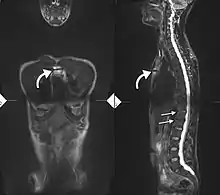

34-year-old male with AS. Inflammatory lesions of the anterior chest wall are shown (curved arrows). Inflammatory changes are seen in the lower thoracic spine and L1 (arrows).

Ankylosing spondylitis is a member of the more broadly defined disease axial spondyloarthritis.[17] Axial spondyloarthritis can be divided into (1) radiographic axial spondyloarthritis (which is a synonym for ankylosing spondylitis) and (2) non-radiographic axial spondyloarthritis (which include less severe forms and early stages of ankylosing spondylitis) [17]

While ankylosing spondylitis can be diagnosed through the description of radiological changes in the sacroiliac joints and spine, there are currently no direct tests (blood or imaging) to unambiguously diagnose early forms of ankylosing spondylitis (non-radiographic axial spondyloarthritis). Diagnosis of non-radiologic axial spondyloarthritis is therefore more difficult and is based on the presence of several typical disease features.[17][18]

If these criteria still do not give a compelling diagnosis magnetic resonance imaging (MRI) may be useful.[17][18] MRI can show inflammation of the sacroiliac joint.